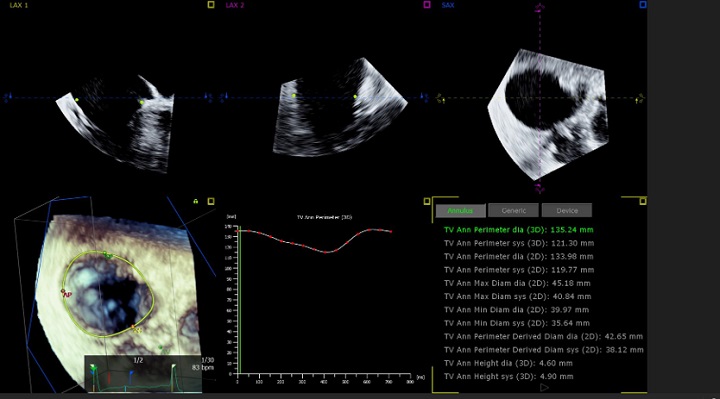

三尖弁解析ツール 三尖弁治療のプランニングに有用なサイジングなどを 3D データから自動で実行するツールです。複雑な三尖弁の解析は従来では手動で行われ、その複雑な形態ゆえにばらつきが大きいものでしたが、AI を使用した 3D Auto TV では再現性高く解析を行うことができます。